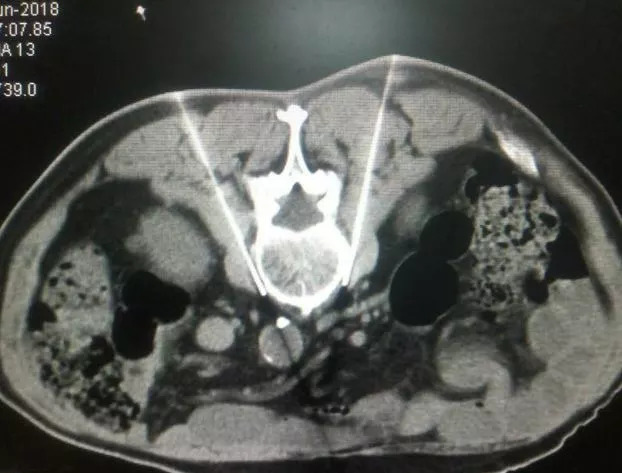

手术叫作:腰交感神经射频。

首先实施脉冲射频术,如症状明显缓解,但疗效不持久, 可行连续射频热凝术。

手术原理:

通过腰交感神经射频,改善下肢血液循环,来治疗不安腿综合征。

脉冲射频电流在神经组织附近形成高电压,但电极尖端温度不超过42度,不会破坏感觉和运动功能,起到神经调制作用。而连续射频热凝通过射频温控治疗仪,使神经局部产生高温,蛋白质变性,影响了疼痛信号传导,有效缓解患者缺血肢体疼痛。

同时,抑制交感神经的传出冲动,扩张缺血区域的小动脉和微动脉,促进缺血区域毛细血管的再生和侧支循环的建立,从而有效改善缺血。